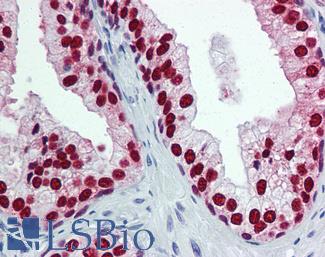

Estrogen Receptor / ESR1

Anti-ER Alpha / Estrogen Receptor antibody IHC staining of human breast. Immunohistochemistry of formalin-fixed, paraffin-embedded tissue after heat-induced antigen retrieval. Antibody LS-B10527 dilution 1:100.